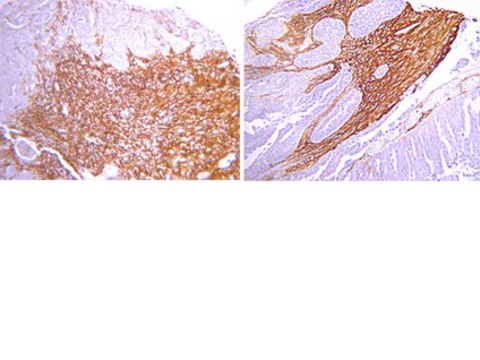

Detect Osteopontin using this Anti-Osteopontin Antibody validated for use in WB, IH.

immunohistochemistry: suitable

The antibody reacts with the 60 kDa osteopontin protein.